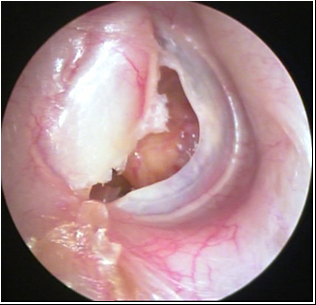

JFC Aticotomía espontánea.